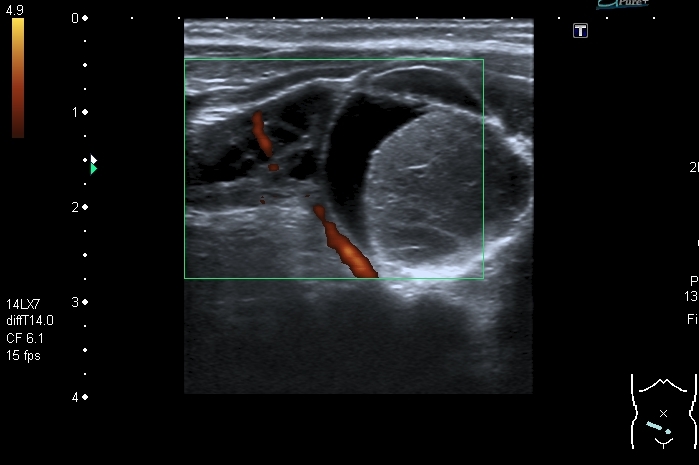

На УЗИ справа от мочевого пузыря - солидно - кистозное образование около 3 см. Образование прилежит к правому яичнику, который визуально не изменён, но смещается относительно его при движениях брюшной стенки Относительно яичника образование гиповаскулярное Выставил диагноз объёмного образования полости таза (дифференцировать энтерокистому и дермоид). Не думаю, что образование исходит из яичника, поэтому стартую тему в гастроэнтерологических исследованиях.

Затронул данную тему, т. к. считаю ультразвуковую семиотику образований яичников и придатков у детей мало изученной , но тем не менее достаточно важной. В моей личной практике клиницисты ставят основной вопрос: откуда образование. Если из яичника или придатков матки - лечат гинекологи. Если из кишечника - лечат хирурги. В данном случае маловероятна непосредственная связь образования с яичником из- за взаимной смещаемости, хотя кистозные тератомы м.б. на ножке. Из придатков матки в доступных мне источниках описаны два варианта образований 1) параовариальные кисты с тонкой стенкой без тканевого компонента - не похоже; 2) гидатида трубы - обычно поменьше.